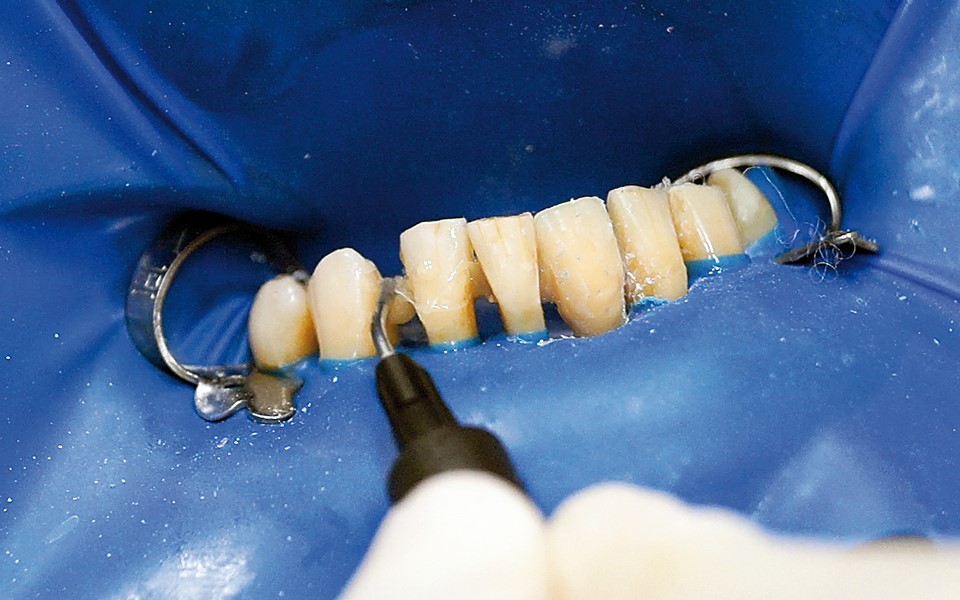

Jedną z popularniejszych metod stabilizacji zębów rozchwianych jest ich szynowanie. Metoda ta, wspierająca inne metody leczenia, jest powszechnie stosowana. Jednym z najnowocześniejszych materiałów wykorzystywanych w stomatologii do szynowania zębów jest taśma poliaramidowa. W opisanym przypadku autorzy pracy przedstawiają sposób uproszczenia całej procedury i ograniczenia ryzyka popełnienia błędu, szczególnie w sytuacji całkowitej utraty zęba. Uzyskano to dzięki zastosowaniu indeksu wykonanego z przezroczystego silikonu.

One of the more popular methods of stabilising loose teeth is to splint them. This method, aiding other methods of treatment, is generally used. One of the most modern materials used in dentistry for splinting teeth, is polyamide tape. In the case described the authors show how to simplify the whole procedure and limit the risk of making a mistake, particularly in the situation of total loss of one tooth. This was achieved thanks to the use of an index made out of transparent silicone.